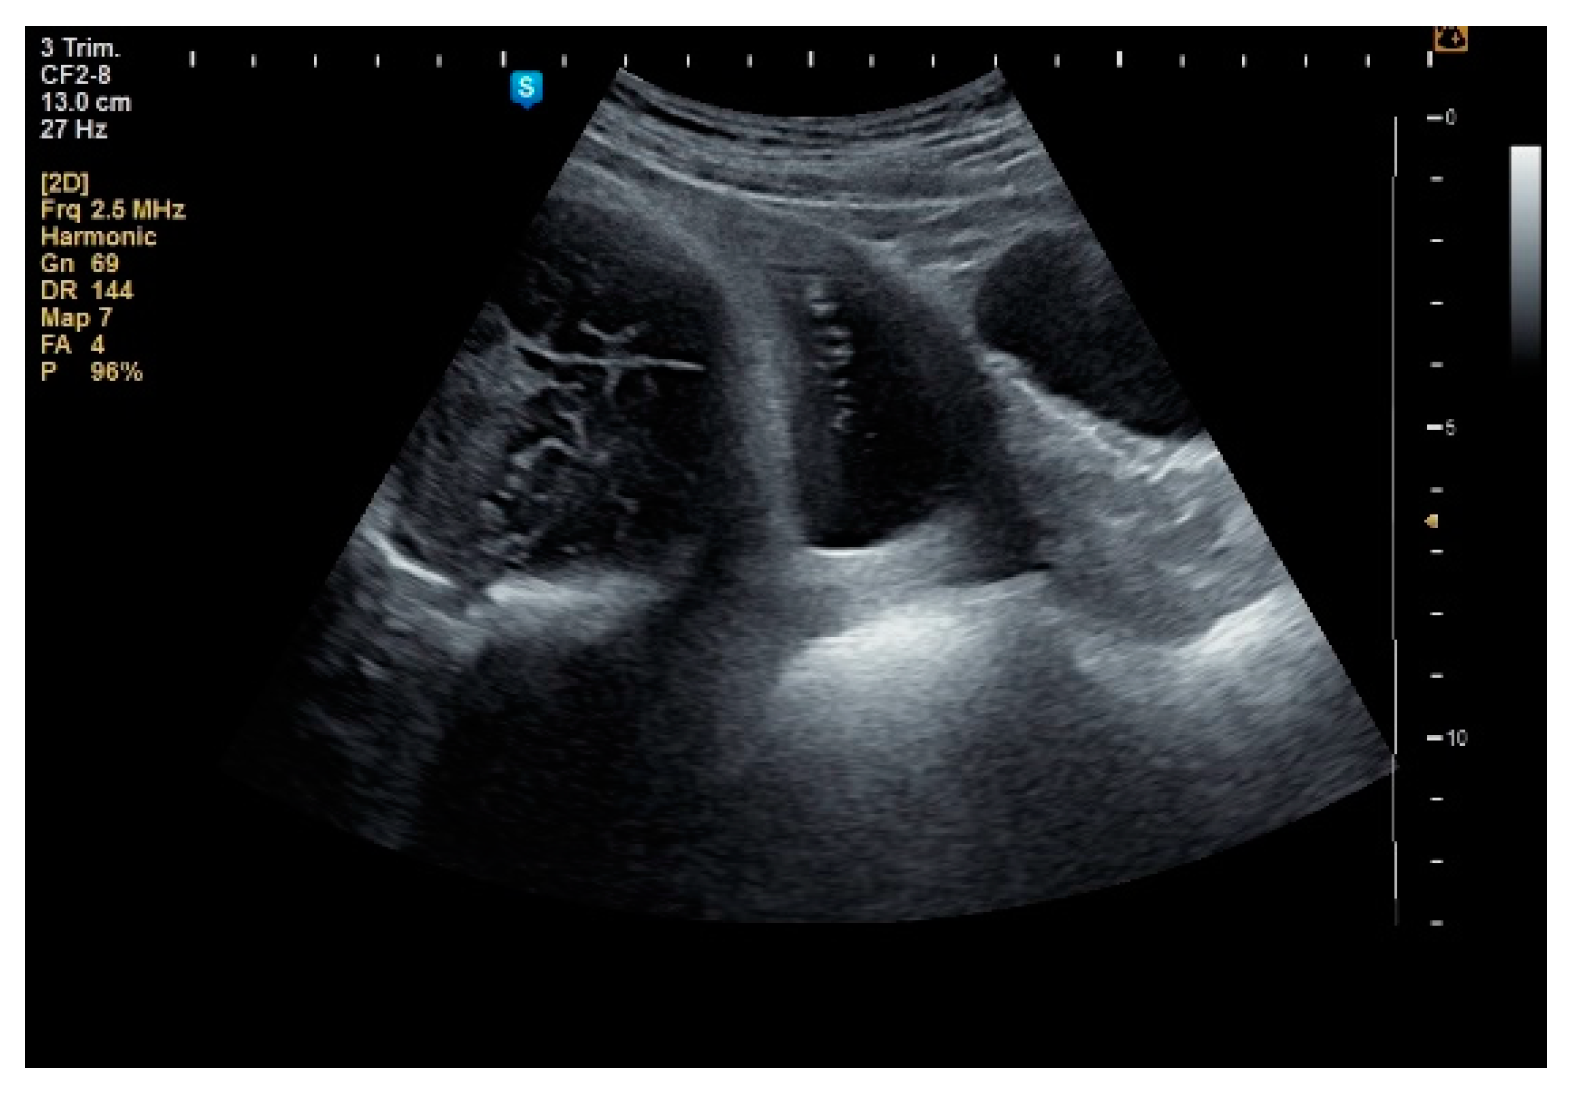

2. Materials and Methods

3. Results